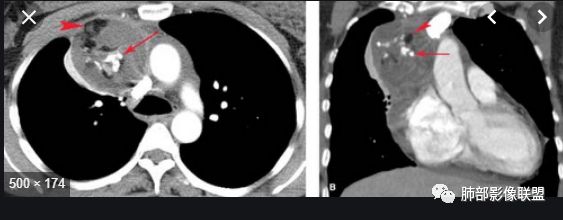

实性部分密度与肌肉类似,钙化粗大、结节状

右侧内乳动脉增粗

实性部分中度强化——增加20~27HU

深分叶,边界尚清,附近未见肿大淋巴结

1.CD钙化不支持,一般条状短棒状为主,小结节

也有,这么大的钙化少见,分叶也太明显。

2.异位甲状腺:发病率低,强化太弱,一般来说异位甲状腺强化达100多

3.神经鞘瘤:深分叶,这么大钙化罕见

所以胸腺瘤首选,其次畸胎瘤,SFT